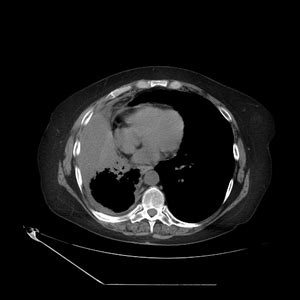

Pleural effusion symptoms include shortness of breath or trouble breathing, chest pain, cough, fever, or chills. Upham j.w., mitchell c.a., armstrong j.g. Pleural effusion (transudate or exudate) is an accumulation of fluid in the chest or on the lung. When you have a pleural effusion, fluid builds up in the space between the layers of your pleura. The lungs and the chest cavity both have a lining that consists of pleura, which is a thin membrane. Simptom clippings rigler (place of entry of the bronchus). Loculated right pleural effusion with foci of atelectasis and consolidative changes concerning for pneumonia. Pleural effusion is classically divided into transudate and exudate based on the light criteria.

Equipment detection of pleural effusion(s) and the creation of an initial differential diagnosis are highly dependent upon imaging of the pleural space. Definitive diagnosis of pleural tuberculosis requires the identification of mycobacteria by microscopy or culture of the pleural fluid or tissue. This procedure applies, in particular, to any case of a first or etiologically unclear pleural effusion. Pleural effusion is the accumulation of pathological fluid in the pleural cavity with inflammatory processes in adjacent organs or pleural sheets or when the ratio between colloid osmotic pressure of the blood plasma and hydrostatic pressure in the capillaries is disturbed. Loculated right pleural effusion with foci of atelectasis and consolidative changes concerning for pneumonia. Most pleural effusions, whether free flowing or loculated, are hypoechoic with a sharp echogenic line that delineates the visceral pleura and lung. Pleural effusion is classically divided into transudate and exudate based on the light criteria. Obliteration of left costophrenic angle with a wide pleural based dome shaped opacity projecting into the lung noted tracking along the cp angle and lateral chest wall suggestive of loculated pleural. N muscular (myofascial, overuse syndromes) n osseous (tumors, infection sickle cell) n articular (sternoclavicular, costovertebral) n neurologic (dorsal roots/zoster, ventral. Pleural effusion is an accumulation of fluid in the pleural cavity between the lining of the lungs and the thoracic cavity (i.e for recurrent pleural effusion or urgent drainage of infected and/or loculated effusions 2526. In slide show mode, to advance slides, press spacebar or click left mouse button. Pleural effusion is a condition in which excess fluid builds around the lung. N adhesions in pleural space.

Patients with pneumonia have a poorer pleural fluid cell count and differential may give important clues as to the underlying diagnosis 10 some patients with fibrous or loculated effusions may also require intrapleural fibrinolytic therapy. Obliteration of left costophrenic angle with a wide pleural based dome shaped opacity projecting into the lung noted tracking along the cp angle and lateral chest wall suggestive of loculated pleural. An elderly male presents following a syncopal event. Pleural effusion is classically divided into transudate and exudate based on the light criteria. When you have a pleural effusion, fluid builds up in the space between the layers of your pleura. Loculated right pleural effusion with foci of atelectasis and consolidative changes concerning for pneumonia. Most pleural effusions, whether free flowing or loculated, are hypoechoic with a sharp echogenic line that delineates the visceral pleura and lung. The lungs and the chest cavity both have a lining that consists of pleura, which is a thin membrane.

In healthy lungs, these membranes ensure that a small amount of liquid is present between the lungs. Leung a.n., muller n.l., miller r.r. Loculated right pleural effusion with foci of atelectasis and consolidative changes concerning for pneumonia. This procedure applies, in particular, to any case of a first or etiologically unclear pleural effusion. Definitive diagnosis of pleural tuberculosis requires the identification of mycobacteria by microscopy or culture of the pleural fluid or tissue.